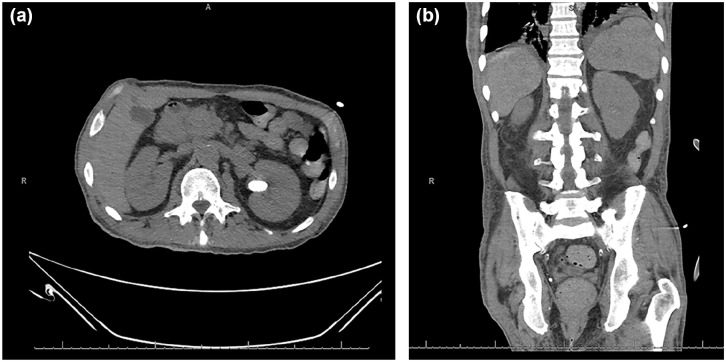

结节病是一种全身性疾病,该病的肺外表现往往无法识别,因为它与许多疾病的表现重叠。终末期肾病(ESRD)可并发高钙血症和脑病,两者都是结节病的潜在症状。这些众多的肺外表现可能延误及时诊断和治疗。在本病例报告中,一名53岁男性ESRD患者在常规血液透析过程中出现无反应发作后入院,后来发现有结节病。最初表现为体温过低、心动过速、白细胞增多和代谢紊乱。支气管肺泡灌洗培养随后生长对甲氧西林敏感的金黄色葡萄球菌,头孢唑林成功治疗。然而,患者仍然患有脑病和高钙血症。进一步检查显示非甲状旁腺激素介导的高钙血症,25-OH维生素D正常,1,25- oh维生素D升高,与结节病、恶性肿瘤或结核病有关。额外的计算机断层成像和支气管超声引导下的活检分别显示淋巴结肿大伴脾肿大和非坏死性肉芽肿,证实结节病的诊断。他开始使用甲基强的松龙、泮托拉唑和甲氧苄啶/磺胺甲恶唑预防耶洛维奇肺囊虫肺炎;血钙水平开始下降,他的精神状态有所改善。虽然他的脑病最初被认为是继发于ESRD和感染,但进一步的检查显示结节病。未经治疗的结节病有显著的健康并发症,包括肺纤维化、肺动脉高压、心律失常和神经功能障碍。由于临床表现可能是多因素的,因此该病例强调了在重症患者的情况下保持广泛区分的重要性。此外,具有复杂病史的患者,如血液透析引起的ESRD,可能使结节病的诊断更加困难。

Sarcoidosis is a systemic disease where extrapulmonary presentation of the disease often goes unrecognized as it overlaps with many disease manifestations. End-stage renal disease (ESRD) can be complicated by hypercalcemia and encephalopathy, both potential signs of sarcoidosis. These numerous extrapulmonary presentations may delay timely diagnosis and treatment. In this case report, a 53-year-old male with ESRD was admitted following an unresponsive episode during routine hemodialysis, later found to have sarcoidosis. Initial presentation notable for hypothermia, tachycardia, leukocytosis, and metabolic derangements. Bronchoalveolar lavage cultures subsequently grew methicillin-sensitive staphylococcus aureus, successfully treated with cefazolin. However, the patient remained encephalopathic and hypercalcemic. Further workup showed nonparathyroid hormone-mediated hypercalcemia with a normal 25-OH vitamin D and elevated 1,25-OH vitamin D, concerning for sarcoidosis, malignancy, or tuberculosis. Additional computed tomography imaging and endobronchial ultrasound-guided biopsy illustrated enlarged lymph nodes with splenomegaly and nonnecrotizing granulomas, respectively, confirming the diagnosis of sarcoidosis. He was started on methylprednisolone, pantoprazole, and trimethoprim/sulfamethoxazole for pneumocystis jirovecii pneumonia prophylaxis; serum calcium levels started to drop, and his mentation improved. While his encephalopathy was initially presumed secondary to his ESRD and infection, further workup revealed sarcoidosis. Untreated sarcoidosis has significant health complications including lung fibrosis, pulmonary hypertension, heart arrhythmias, and neurological deficits. This case highlights the importance of maintaining a broad differential in the setting of critically ill patients as clinical presentations can be multifactorial. Furthermore, patients with a complex medical history such as ESRD on hemodialysis can make concluding sarcoidosis as a diagnosis more difficult.